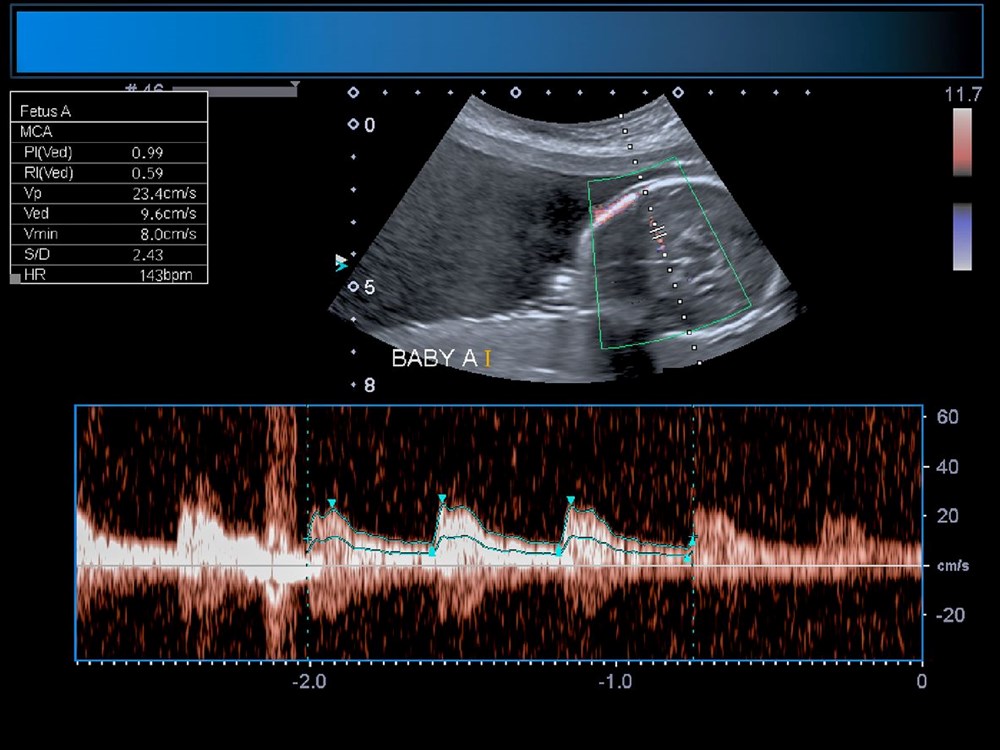

Anneyi 34. haftada ameliyat eden bilim insanları, operasyonu yönlendirmek için ultrason kullandı.

Diğer taraftan, operasyon kapsamında 10 sağlık görevlisinden oluşan bir ekip, annenin karnından uzun bir iğneyi bebeğin beyninin arterlerin etkilendiği kısmına yönlendirmek için ultrason kullandı. Doktorlar, daha sonra damarlara geri akışı engellemek için damar içine küçük bir madde enjekte etti.